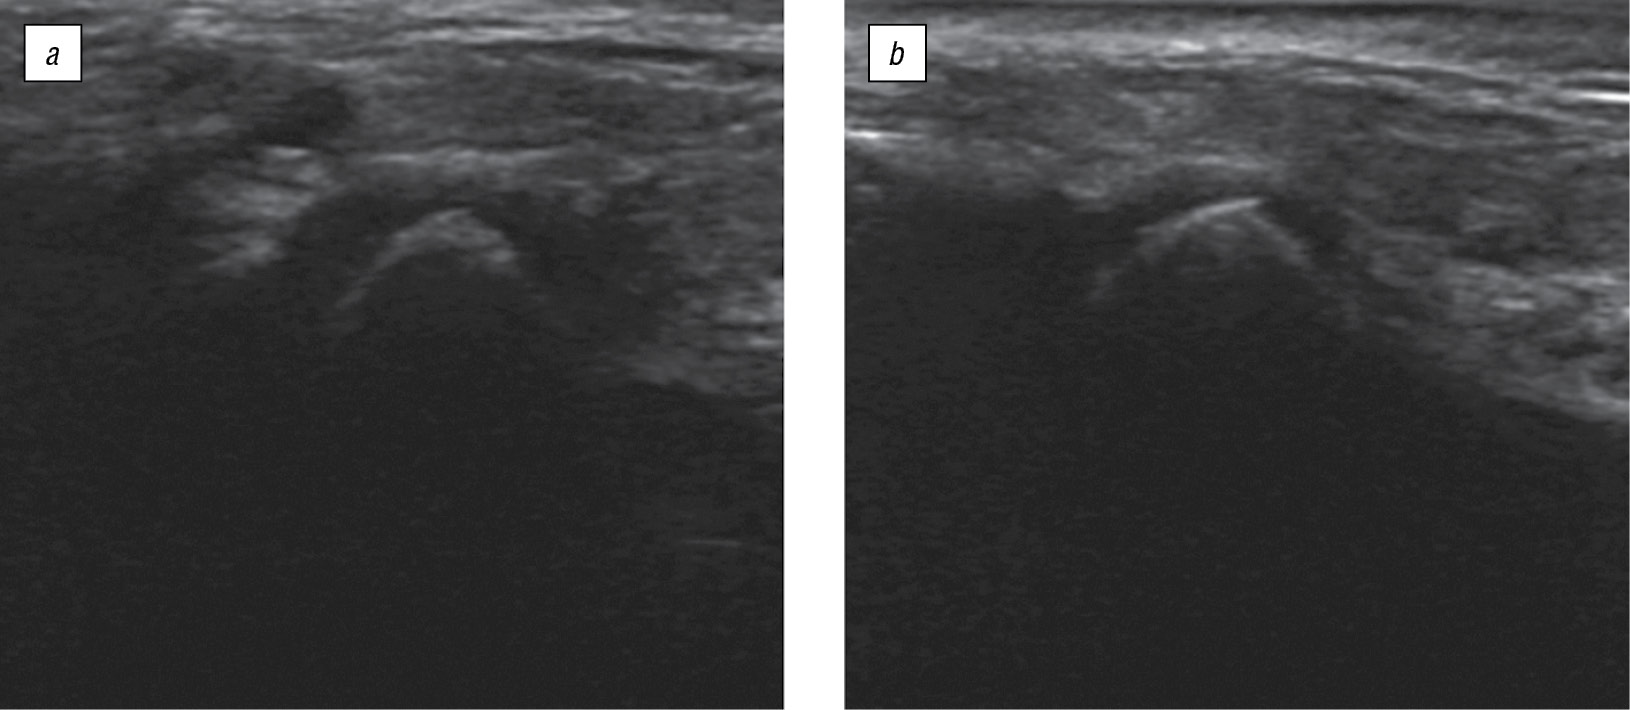

Полученные данные КЛКТ позволяют говорить о возможном изменении состояния окружающих сустав мягкотканных структур, нарушении дислокации суставного диска ВНЧС и нарушении функционирования ВНЧС. Для дальнейшего уточнения поставленного диагноза было проведено УЗИ ВНЧС (рис. 8).

Рис. 8. Ультразвуковое исследование височно-нижнечелюстного сустава пациента П., 15 лет: a — справа; b — слева / Fig. 8. Ultrasound of the temporomandibular joint, patient P., 15 years old: a — on the right; b — on the left

По полученным результатам с обеих сторон определяется: неровность контуров головок нижней челюсти с участками повышенной и пониженной эхогенности, что говорит об изменении гиалинового хряща суставной поверхности; значительное уменьшение капсульно-шеечного пространства, когда капсула сустава имеет неровный, нечеткий контур, уплощенную форму; амплитуды движения нижней челюсти в пределах нормы; латеральные крыловидные мышцы не изменены. При открывании рта наблюдается проскакивание головки на свое привычное положение через задний полюс суставного диска, при этом возникает щелчок, в конце закрывания рта суставная головка перемещается кзади от диска, пока не наступит смыкание зубных рядов, при этом диск со вторым щелчком оттесняется головкой кпереди.

Уточненный диагноз: дистальная окклюзия, гнатическая форма, сужение заднего отдела суставной щели ВНЧС, дистальное смещение головок нижней челюсти, вентральная дислокация суставного диска.